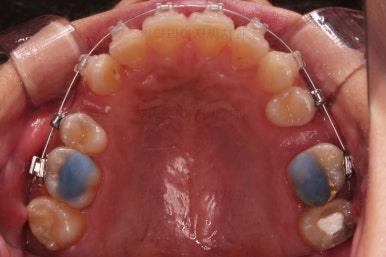

1. 초진

연산동교정치과 초진 시 입안의 모습입니다.

얼핏 앞에서 봤을 때 치열이 나쁘지 않아 보이는데요.

대신 자세히 살펴보면 윗니 양쪽 송곳니가 덧니처럼 볼록 튀어나와 있고요.

아랫니 어금니가 하나 없어서 주위 치아들이 해당 위치로 쓰러진 상태였습니다.

그리고 양쪽의 교합이 톱니바퀴처럼 맞물려 있는 것 같지만 톱니바퀴가 한 칸씩 밀려서 맞물려 있는 부정교합이 있는 상태였습니다.

장치를 부착했고요.

이번에 환자분이 선택한 장치는 윗니는 자가결찰 세라믹, 아랫니는 자가결찰 메탈이었습니다.

이렇게 혼용해서 사용해도 되는 조합들이 있고요.

이번 환자분은 웃을 때 이가 많이 보이는 타입이 아니셔서 아랫니는 좀 더 튼튼하고 저렴하기까지한 메탈장치를 선택하셨죠.